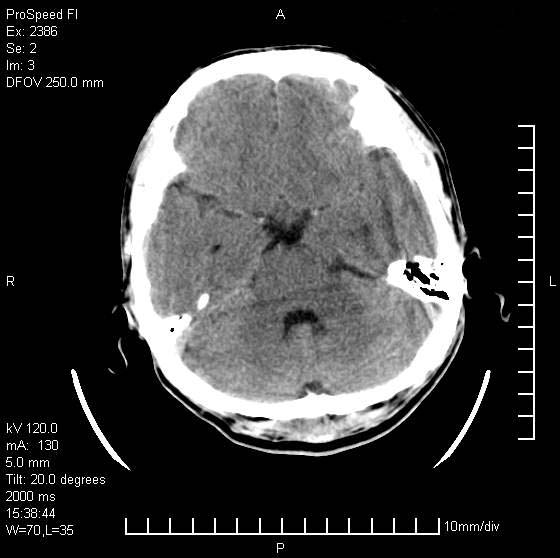

以下是引用天南地北在2007-9-19 18:43:00的发言:[br]典型慢性硬膜外血肿[br][br][本贴已被 天南地北 于 2007-9-19 18:44:11 修改过]

以下是引用曼一拍在2007-9-20 11:06:00的发言:[br]支持慢性硬膜下血肿.[br]慢性硬膜下积液:血肿有包膜,ct值稍高于脑脊液,增强可有染色。不典型者血肿可多呈梭形.是硬脑膜与蛛网膜之间的潜在腔隙内的血肿。[br]鉴别:[br]1\\硬膜外血肿:是颅脑外伤后脑膜或板障内血管破裂,血液在颅骨与硬膜之间积聚所致.通常是脑膜动脉破裂,也可因静脉窦破裂或颅骨的板障静脉出血,发生于外伤的着力部,常与颅骨骨折并存。脑膜动脉出血则急,若是板障静脉出血在则可有慢性。[br]2\\硬膜下积液:(硬膜下水瘤)[br]是由于蛛网膜破裂,脑脊液经蛛网膜破口进入硬膜下腔不能回流。或水肿阻塞而形成。[br]ct表现:颅骨内板下方新月形低密度区近似脑脊液密度;占位效应清,周围无脑水肿。[br]